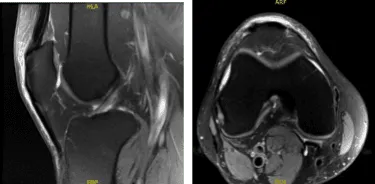

MRI-3t Rodilla derecha sin contraste

No hay desgarro meniscal ni lesión de ligamentos. El cartílago se conserva. En la rodilla derecha, los resultados de la radiografía han mostrado desgarro superficial bajo la parte inferior en la unión del cuerno posterior/cuerpo del menisco medial y deshilachamiento inferior del cuerno posterior.

Cuádriceps leve y tendinosis rotuliana, sin desgarro. Bursitis prepateliana leve y edema moderado de tejidos blandos circundantes. Hablamos del tratamiento con el paciente. El paciente había probado fisioterapia en el pasado.